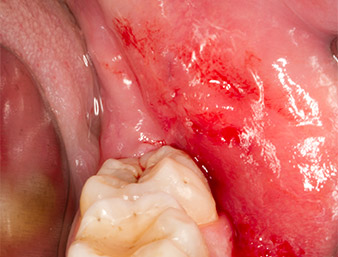

Tras una anestesia local y por conducción, el campo quirúrgico se abrió mediante los tejidos blandos para tener un acceso bucal-retromolar y se dejó expuesto (figura 3).

El tejido situado por encima del resto radicular no se había osificado por completo y constaba en su mayor parte de un tejido granulado con alteraciones inflamatorias (figura 4).